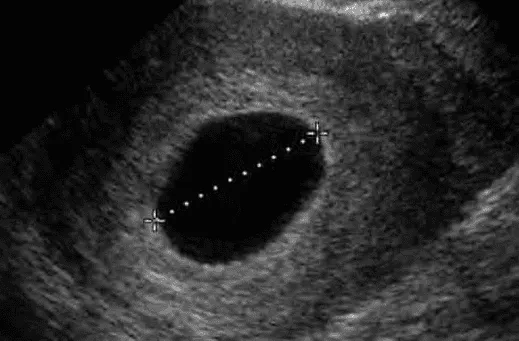

Để chẩn đoán trứng trống, không đủ khi chỉ không thấy phôi hoặc túi noãn hoàng với MSD < 25 mm. Phải có MSD ≥ 25 mm không thấy phôi hoặc túi noãn hoàng.

- MSD ≥ 25 mm không thấy phôi thai.